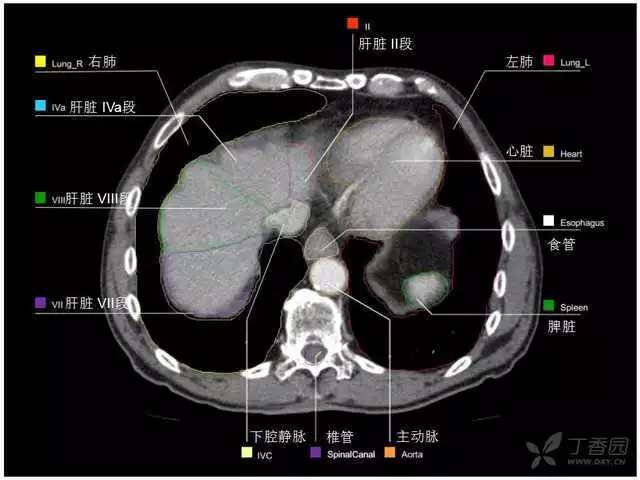

其实你离掌握上腹部 CT 影像只有一套高清实用图谱的距离,下面把我最喜欢的这本图谱分享给大家,为了方便阅读,我加了中文标识。后面附赠几张血管相对位置解剖关系图片,帮助大家理解(文中多图,建议在 wifi 环境下查看)。